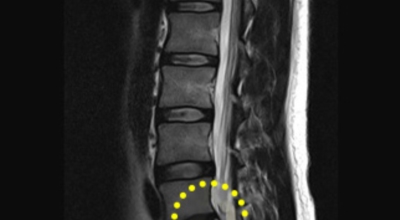

경추 사이의 추간판(디스크)이 탈출 또는 파열되어 경추신경이 자극이나 압박을 받아 통증이 생기는 증상을 말해요. 경추는 운동성이 큰 부위로 추간판이 압력을 받으면 튀어나와 척수나 신경을 압박하게 되는데요 목디스크는 퇴행성 변화 이후에 발생되기 때문에 많은 환자들이 만성적인 통증을 지니고 있는 경우가 많아요. 급성으로 생기는 경우는 교통사고, 추락, 스포츠 활동에 의한 목 부상으로 나타나기도 해요. 20대부터 가벼운 초기 증상으로 시작하여 옳지 않은 습관으로 악화되거나 호전되기를 반복해요. 나이가 들면 퇴행성 변화로 40~50대에 가장 많은 환자 수를 보인다고 합니다

비수술적 치료가 효과가 없다거나 디스크의 신경압박이 정도가 심한 경우엔 시술할 관조차 들어갈 공간이 없으니 비수술을 고집하는 경우 주변의 정상조직까지 훼손이 될 위험이 있답니다. 미세 현미경 수술이나 인공 디스크 치환술 및 경추유합술을 통해서 치료가 가능한데 가급적 비수술치료가 권장되지만 정확한 진단이 먼저되어야 하기 때문에 자세한 사항은 전문의와 상담해서 결정하는 것이 좋을겁니다.